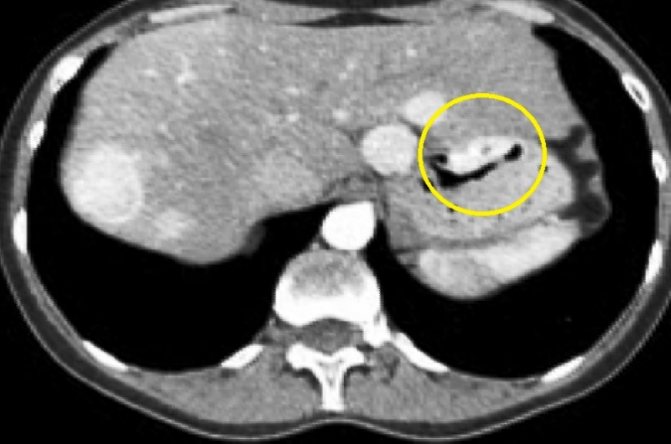

О том, как очаги могут выглядеть на снимках КТ и МРТ, а также как не перепутать на вид разные заболевания, читайте в статье про гиподенсные образования в печени.

Эхогенное образование в печени на УЗИ может быть диффузным и местным. Диффузная гипоэхогенность, указывает на воспалительный процесс, очаговая может служить признаком кисты, абсцесса. Надо также помнить, что крупные сосуды также выглядят гипоэхогенными с плотной сосудистой оболочкой. Очаговый характер изменений обычно указывает на злокачественные и доброкачественные новообразования, кистозные изменения.

На томограмме такой объект имеет более светлый вид, в сравнении с близлежащими тканями.